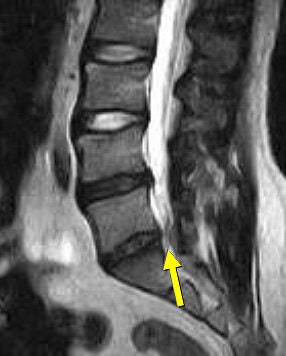

![]() |

| Above and below, axial-load study. L5-S1 anterolisthesis increases from 4 mm to 5 mm with axial loading. L4-L5 retrolisthesis increases from 3 mm to 4 mm with axial loading Mild central spinal canal narrowing. |